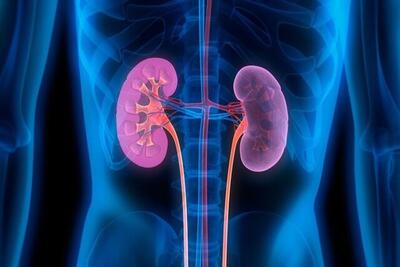

۱۴۰۳/۰۸/۲۸ / روزنامه تعادل

اهمیت تستهای سالانه عملکرد کلیوی از ۴۰ سالگی به بعد

نارسایی مزمن کلیه یک بیماری خاموش است که فرد مبتلا ممکن است سالها از آن بیاطلاع باشد؛ علل ایجاد کننده این بیماری، اغلب به بیماریهای دیابت و فشار خون بالا بازمیگردد.